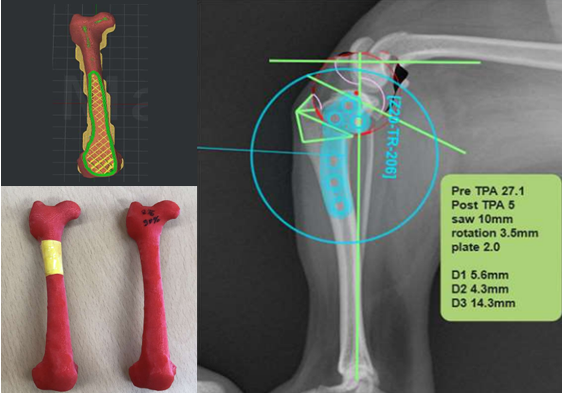

방사선 촬영(X-ray), 초음파, CT 등 다양한 영상 장비를 활용하여 진단을 수행합니다. 특히 CT 데이터를 기반으로 3D 뼈 모형을 재구성함으로써 복잡한 뼈 변형과 관절 구조를 입체적으로 분석할 수 있습니다. 이를 통해 수술 전 시뮬레이션을 진행하여 오차를 최소화합니다.

전십자인대 파열은 반려견에서 가장 흔한 무릎 관절 질환으로, 심할 경우 보행이 어렵고 심한 통증을 유발합니다. 본원은 뼈 구조, 체중, 활동 수준 등을 고려하여 TPLO, CTWO 등 다양한 수술 방법 중 가장 적합한 수술법을 선택해 맞춤 치료를 진행합니다. X-ray와 CT 영상을 통해 인대 손상 정도와 관절 상태를 정밀하게 진단하고, 수술 전 시뮬레이션을 통해 오차를 최소화합니다. 수술 후에는 통증 관리와 재활 운동, 근력 강화 프로그램을 통해 기능 회복을 돕고 재발을 예방합니다.

선천성 기형 및 사지 변형은 반려동물의 정상적인 사지 성장과 기능에 영향을 미치는 문제로, 본원에서는 3D CT 기반의 정밀한 분석을 통해 변형 부위를 정확히 진단하고, 교정 절골술을 시행하여 정상적인 골격 구조와 움직임 회복을 목표로 치료합니다.